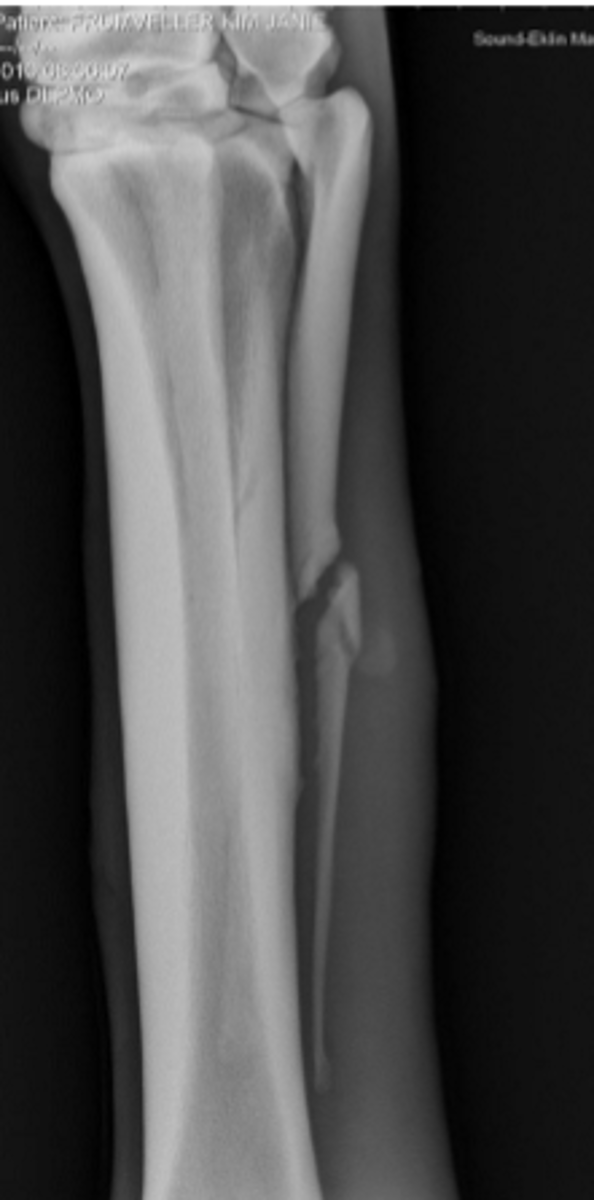

Transfixation pin cast

What is this radiograph depicting?

P3

What bone is fractured?

Foot cast

What type of coaptation would you apply for healing?

Suspensory ligament

What structure caused the avulsion?

Remove the middle section of the bone to remove the fracture

How is this fracture treated?